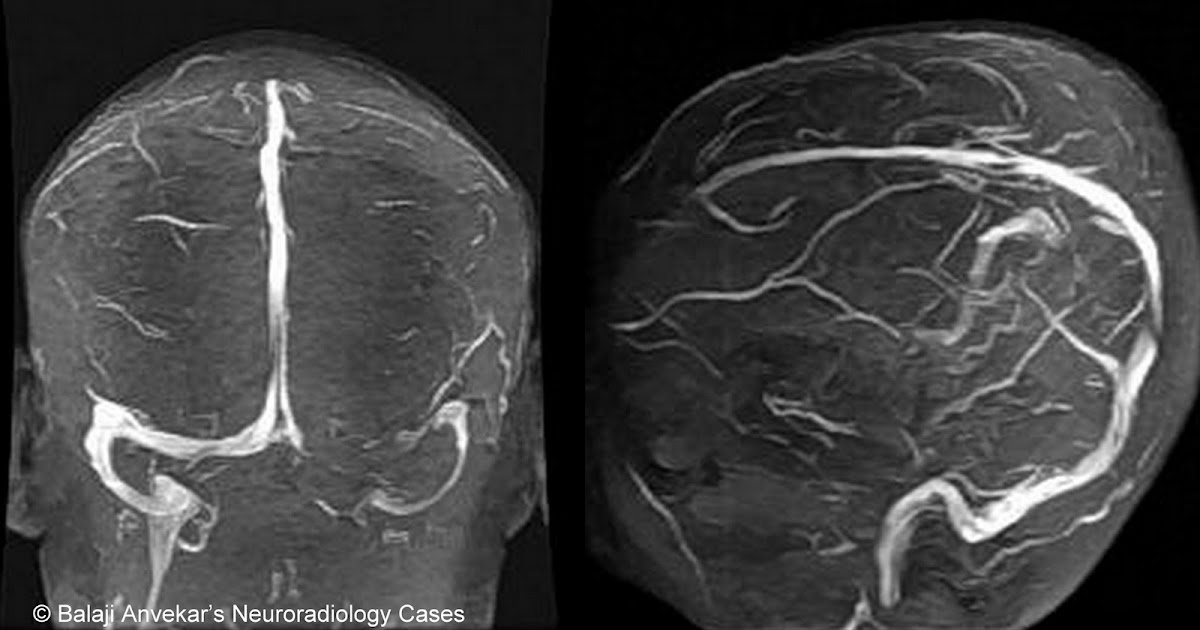

From www.neuroradiologycases.com

Neuroradiology Cases Hypoplastic transverse sinus MRI Sigmoid Sinus Meaning identifying hypoplastic sigmoid sinus symptoms, along with those affecting the right transverse sinus, is imperative for those experiencing unexplained. Sigmoid sinuses) is a paired structure and one of the dural venous sinuses. the sigmoid sinus receives the mastoid and condylar emissary veins. It also receives blood from the cerebral, cerebellar, and diploic veins. the sigmoid sinus is. Sigmoid Sinus Meaning.